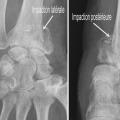

Au niveau métaphysaire le déplacement peut être postérieur ou antérieur (fig. 6). En ce qui concerne le déplacement postérieur, il est important de se souvenir que la surface articulaire regarde vers l’avant. En d’autres termes, dès que cela n’est plus le cas, même si la surface articulaire n’est pas orientée vers l’arrière, il s’agit d’un déplacement postérieur. Classiquement, le déplacement postérieur est lié à un mécanisme dit en compression-­extension, c’est-à-dire une chute sur la main, le poignet étant en extension (fig. 7). Le déplacement est dit antérieur s’il y a une exagération de l’orientation antérieure de l’épiphyse radiale. Ce déplacement est classiquement lié à un mécanisme dit en compression-flexion, c’est-à-dire une chute sur la main, le poignet étant en flexion (fig. 7). La plupart du temps, ce déplacement postérieur ou antérieur s’accompagne également d’un déplacement externe, avec un tassement au niveau de la corticale latérale (fig. 8). Outre le déplacement antérieur, postérieur ou latéral, il est très important d’analyser au niveau du foyer de fracture métaphysaire l’importance de la comminution qui peut être uniquement postérieure, ou antérieure, ou circonférentielle, ce qui conditionne la stabilité de la fracture et oriente vers le type d’ostéosynthèse à réaliser.